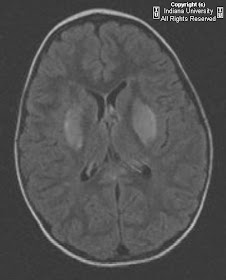

Findings

CT head: Low attenuation in the bilateral basal ganglia

MRI brain: There are small focal areas of diffusion restriction in the periventricular white matter, bilateral thalami and putamen. There is T2 prolongation affecting the basal ganglia, corpus callosum (genu and splenium), external capsules, and corona radiata.

Imaging (MRI)

Basal ganglia T2 hyper intensity is the most common finding, particularly the dorsal lateral lentiform nuclei.

T2 weighted hyper intensities have been reported to involved the thalamus, internal and external capsules, dorsal brainstem, corpus callosum, posterior leukoencephalopathy syndrome. Findings likely related to edema.

Diffusion restriction in the basal ganglia and thalami has been reported.